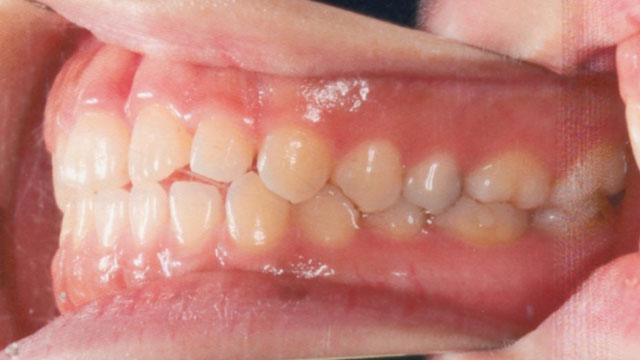

症例02【空隙歯列】

16歳9か月(男子)

上下の顎の成長・発育のバランスには問題はなく、骨格的な不調和は認められませんでした。

ただし、歯の大きさが平均よりもやや小さいことに加え、舌で前歯を押し出す癖(舌突出癖)がみられ、これが前歯の位置に影響している状態でした。

そのため、治療計画は非抜歯とし、スタンダードエッジワイズ法による矯正治療を選択。

治療期間は1年11か月で、その後は保定へ移行。

- 空隙歯列